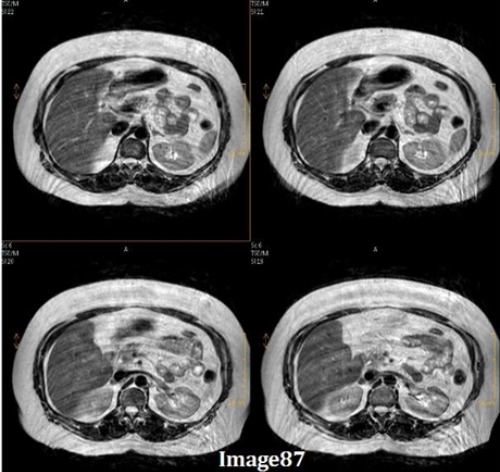

Image 86 is an example of which kind of artifact?

A. Motion/ghosting in the phase direction

B. Gibbs truncation

C. Dielectric effects

D. RF zipper

E. Magnetic susceptibility